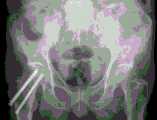

FIG. 4 is a diagram of a femoral neck fracture normal position X-ray

FIG. 6 is a multi-tunnel nail-implanting drawing for femoral neck fracture

When the image correction and calibration module receives an X-ray image (a femur neck fracture normal X-ray diagram in fig. 4 and a femur neck fracture lateral X-ray diagram in fig. 5), firstly correcting the image and then calculating calibration parameters. The specific execution steps are as follows:

k: the doctor implants the nail along the axial direction of the tunnelposition indication end 4, and the X-ray film is shot after the nail is implanted, as shown in figure 6.